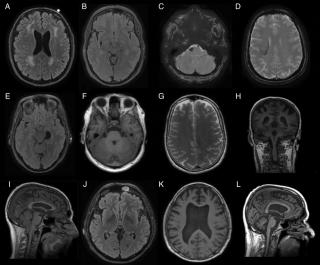

Методом выбора является МРТ с контрастным усилением, с получением диффузионно-взвешенных изображений. Наиболее значимый диагностический признаком является гиперинтенсивность паренхимы спинного мозга на Т2-ВИ с центральной зоной напоминающий «совиный глаз». Гиперинтенсивность центрального серого вещества спинного мозга в Т2-режиме, изменения периферических участков паренхимы спинного мозга более вариабельны.

Т1-ВИ

Некоторое утолщение спинного мозга. Атрофия спинного мозга в отдаленном периоде. Геморрагическая конверсия зоны инфаркта, как следствие гиперинтенсивность сигнала (редко).

Т2-ВИ

Гиперинтенсивность центрального серого вещества или всего поперечника спинного мозга

Диффузно-взвешенное изображение

Гиперинтенсивность сигнала, как при инфарктах головного мозга